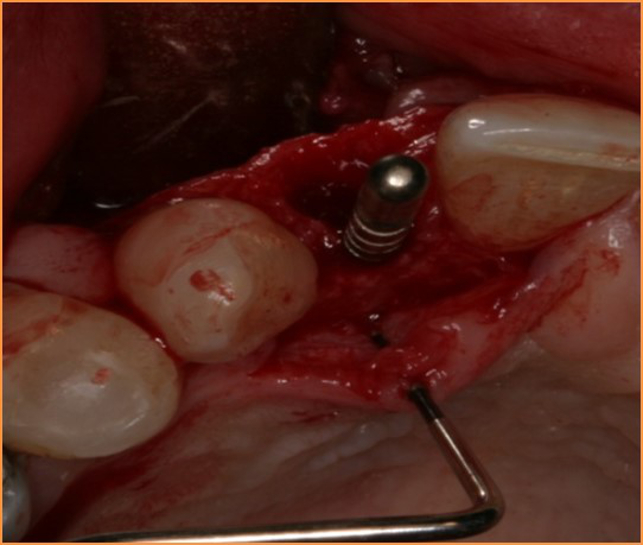

Fotos dos casos clínicos